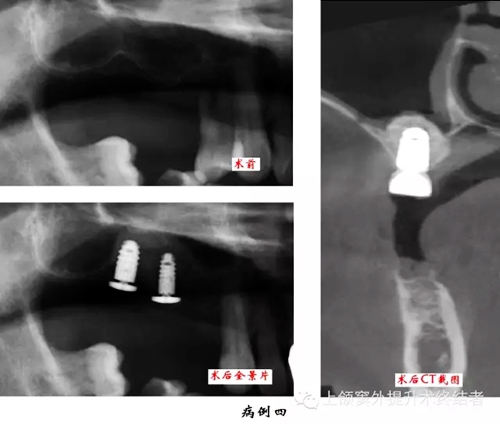

術(shù)前檢查口腔內(nèi)情況,主要包括骨和粘膜的狀況。拍攝曲體層片,測(cè)量并按其放大率計(jì)數(shù)上頜竇底至牙槽嵴頂?shù)木嚯x,檢查上頜竇形態(tài)和密度,排除無(wú)癥狀的上頜竇慢性炎癥或囊腫等。觀察竇內(nèi)有無(wú)上頜竇橫隔,位置是否影響手術(shù)操作,如有影響則需調(diào)整開窗位置。拍攝直線體層片和上頜竇矢狀面體層片可以顯示上頜竇底斷面或矢狀面的現(xiàn)狀,但以上圖像都有一定程度的放大失真。如有條件采用三維螺旋CT進(jìn)行掃描可以準(zhǔn)確測(cè)量上頜竇底至牙槽嵴頂?shù)膶?shí)際距離,觀察上頜骨形態(tài),分析術(shù)區(qū)條件和檢查上頜竇健康狀況,以利于進(jìn)行術(shù)前診斷和制定治療計(jì)劃。上頜竇底提升同期種植術(shù)前應(yīng)制作手術(shù)模板。